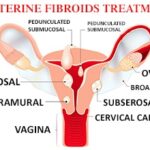

All You Need to Know About Fibroid Treatments

Author –Dr Preety Aggarwal MBBS, DGO, DNB, Medical Director (Gurgaon)- Obstetrics and Gynaecology. All You Need to Know About Fibroid Treatments Treatment for fibroids can range from no treatment at all to surgery. Usually, small fibroids do not cause any symptoms and are not treated. The big fibroids, on the other hand, show symptoms including […]

Fibroids: Symptoms and Treatments

Author –Dr Preety Aggarwal MBBS, DGO, DNB, Medical Director (Gurgaon)- Obstetrics and Gynaecology Fibroids: Symptoms and Treatments Introduction Fibroids or Uterine fibroids refer to the abnormal growth in or on the uterus. These are non-cancerous tumours that might not even go unnoticed for several years. According to Dr Preety Aggarwal, MBBS, DGO, DNB, Medical Director (Gurgaon)- […]

What is Infertility in Fibroids?

Author – Dr Poonam Garg Consultant – Obstetrician, Gynaecologist at Motherhood Chaitanya Hospital, Chandigarh Infertility in Fibroids Infertility is an important social and economic problem today because a lot of couples plan their families much later in life. With increasing age, the chances of women getting pregnant are fewer and may be less likely to […]